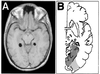

Studies of patients with focal brain damage suggest that topographical representation is subserved by dissociable neural subcomponents. This article offers a condensed review of the literature of "topographical disorientation" and describes several functional MRI studies designed to test hypotheses generated by that review. Three hypotheses are considered: (i) The parahippocampal cortex is critically involved in the acquisition of exocentric spatial information in humans; (ii) separable, posterior, dorsal, and ventral cortical regions subserve the perception and long term representation of position and identity, respectively, of landmarks; and (iii) there is a distinct area of the ventral occipitotemporal cortex that responds maximally to building stimuli and may play a role in the perception of salient landmarks. We conclude with a discussion of the inferential limitations of neuroimaging and lesion studies. It is proposed that combining these two approaches allows for inferences regarding the computational involvement of a neuroanatomical substrate in a given cognitive process although neither method can strictly support this conclusion alone.